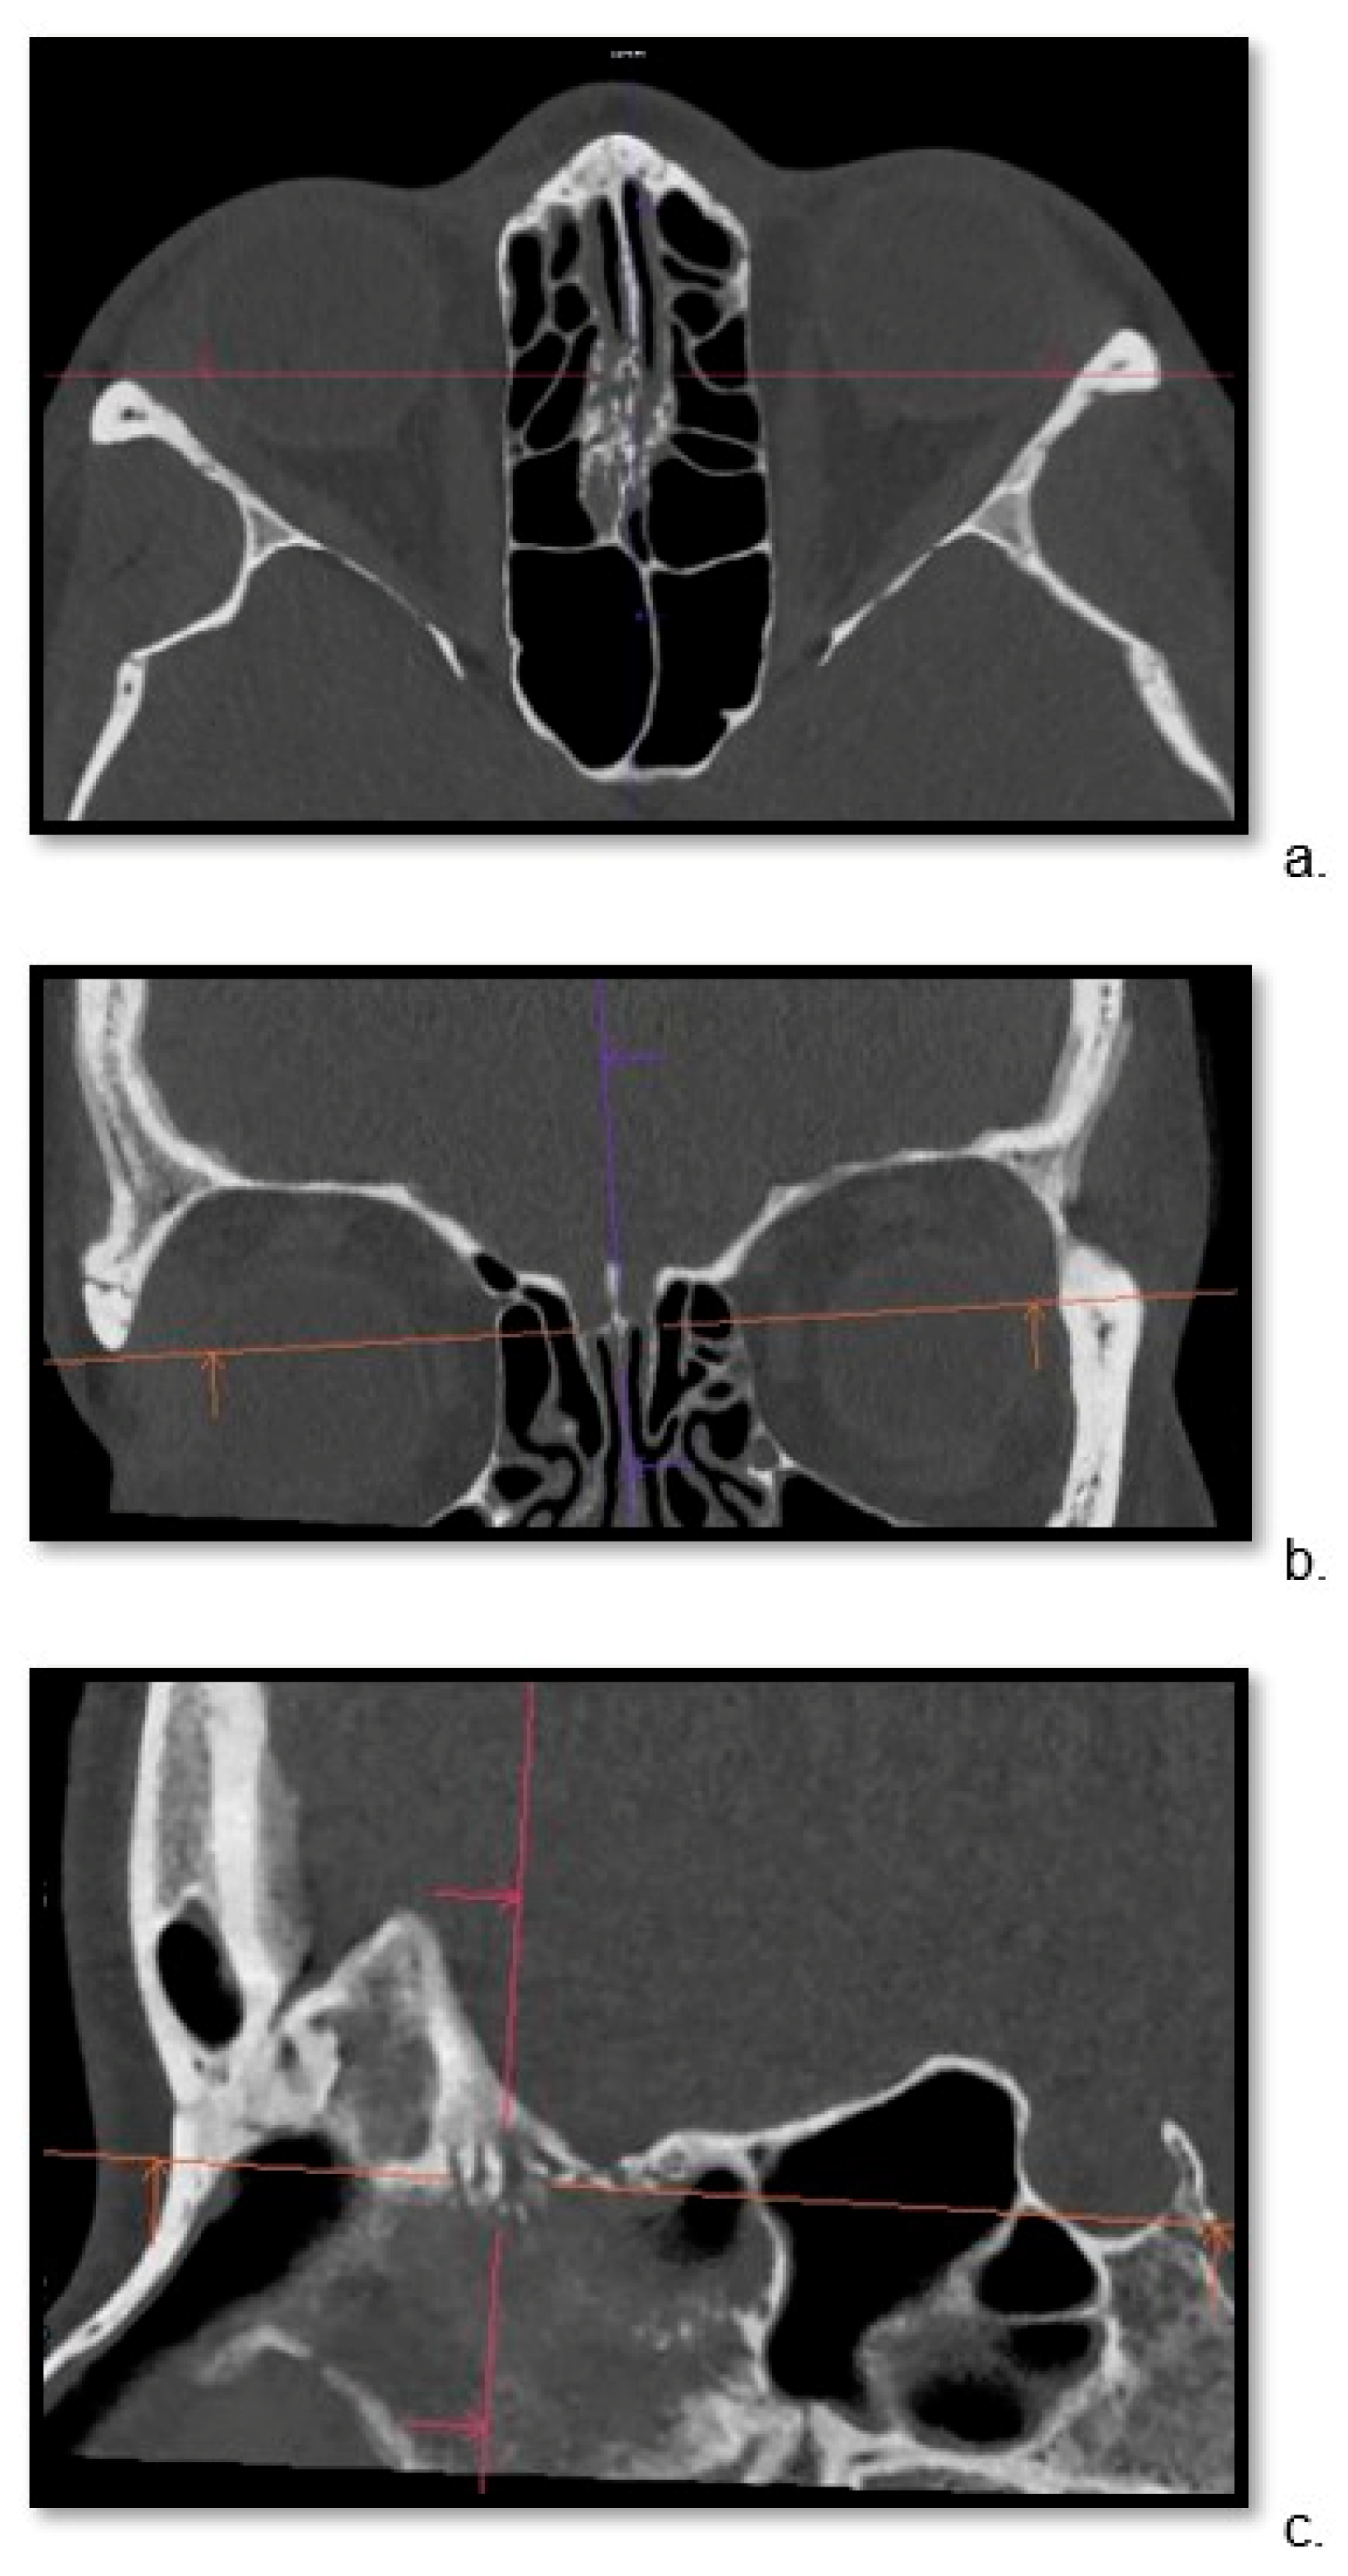

2.3. Image Preparation—Multiplanar Reconstructions